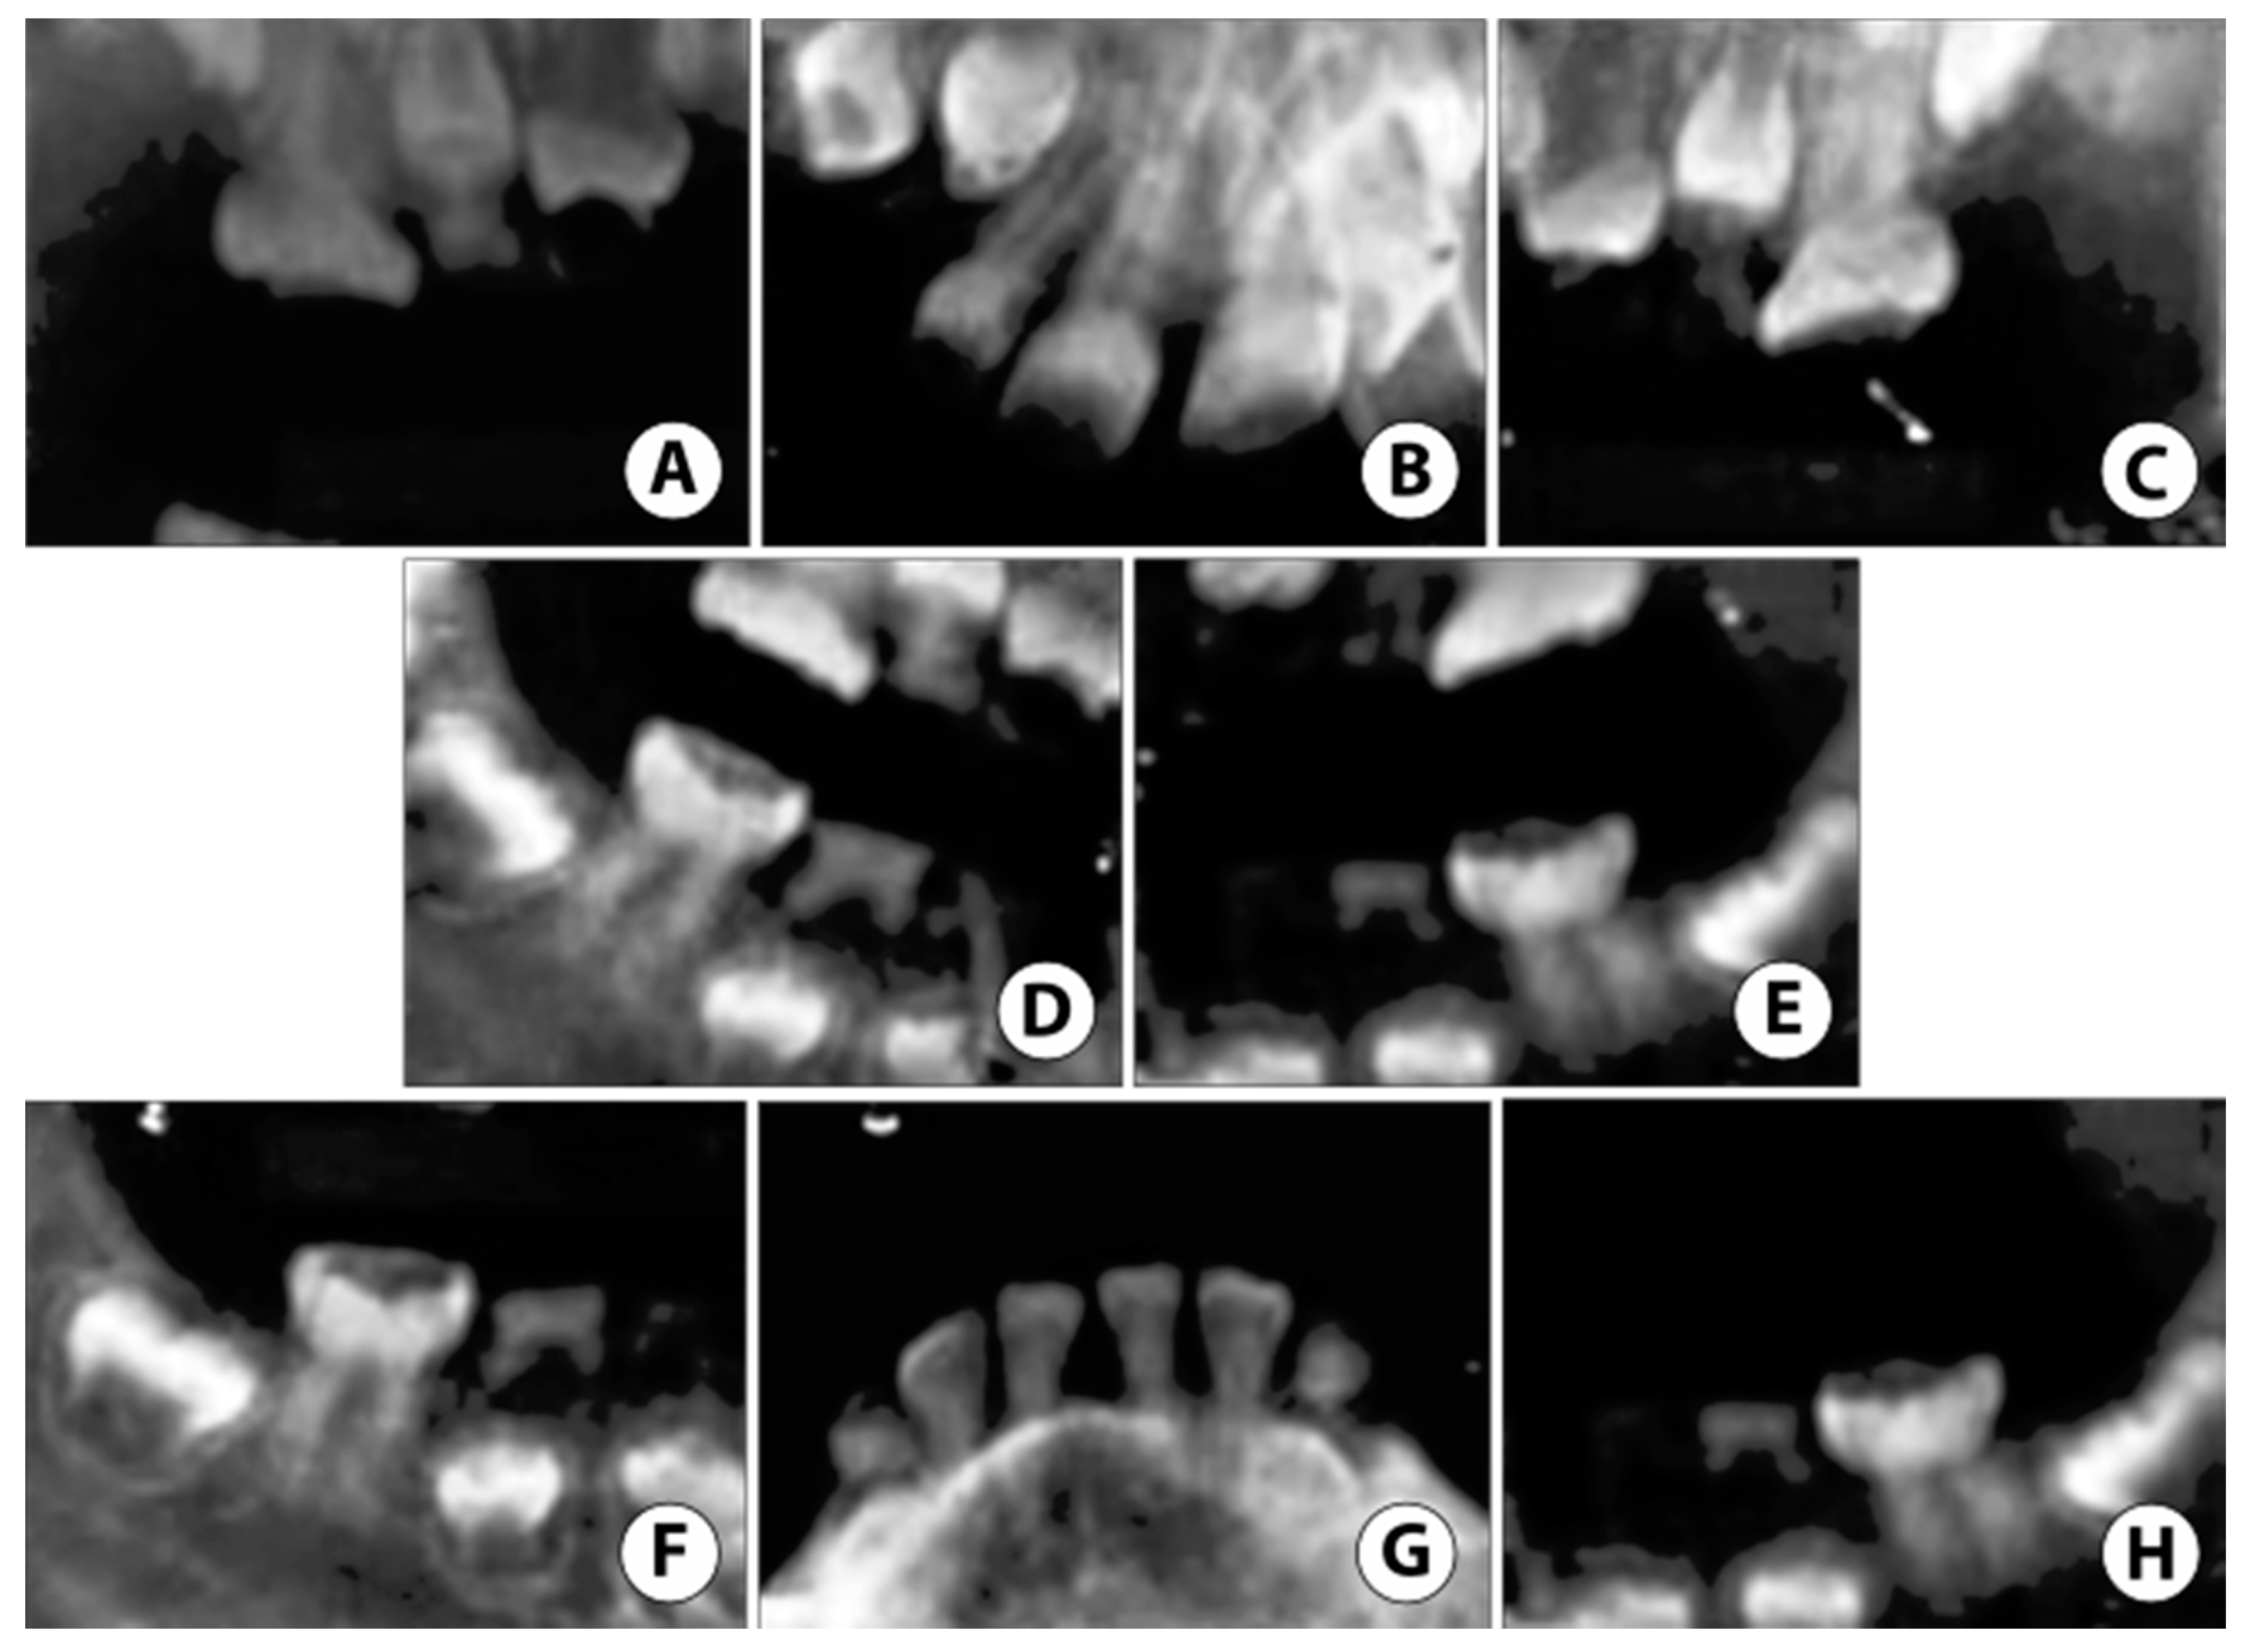

Due to prior ineffective OCS and severe ASD, treatment under General Anesthesia (GA) was accepted as the best method to restore the patient’s oral health. Under GA, a full set of radiographs were taken (Figure 5), along with intraoral photographs (Figure 6), which revealed an irregular/extensive caries pattern extending to the cusp on all permanent first molars due to attrition and poor enamel to dentin strength associated with DGI-II. The patient had amber-hue colored anterior teeth with most enamel missing and attrition down to the gingival margin on all primary first and second molars, and caries were present on the facial surface of all upper and lower anterior incisors as seen in Figure 6.

Figure 5.

Case 2: Non-digital radiographs taken in the hospital under General Anesthesia (GA) reveal (A–C) severe enamel loss with reduced pulp space in both primary and permanent teeth. (D,E) Root tip fragments of upper primary canines noted. (F,H) Extensive atypical occlusal caries noted on lower permanent first molars. (G) Reduced pulp space in permanent mandibular incisors with near exfoliation of lower primary canines.